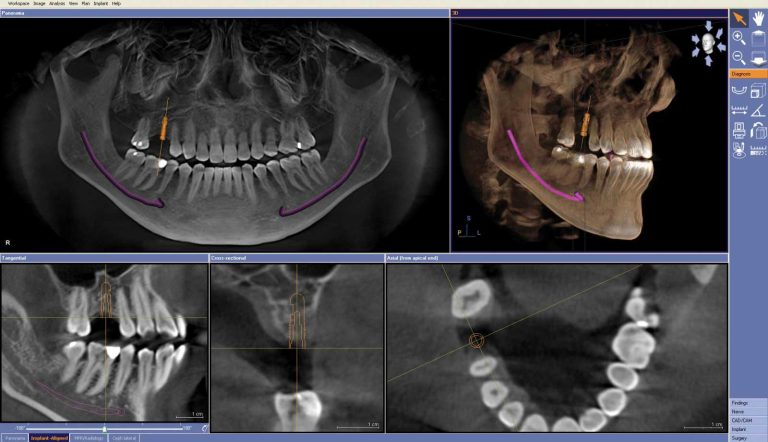

Calismiles is now offering advanced three-dimensional dental imaging to provide patients with the best treatment possible.

This dental imaging technology is particularly useful for dental implant treatment planning, root canal therapy, TMJ and other complex procedures, offering a quick scan that improves the opportunity to catch issues early.

This scanning process takes only 14 seconds and provides detailed images that increase clinical safety. The doctor will review the scan with the patient, using the rotating and moving image capabilities to enhance visibility.

By using this advanced technology, patients can easily see their teeth, upper and lower jaws, sinuses, and any issues that need immediate attention.

Overall, this 3D dental imaging system provides reliable and accurate results that ultimately improve patient care and satisfaction.